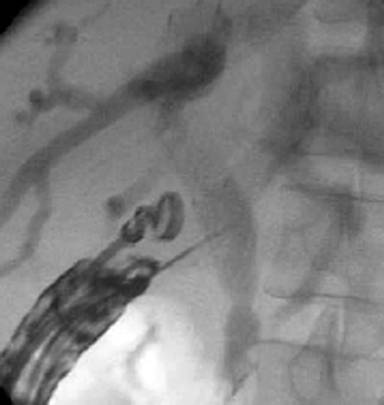

To confirm successful biliary access, the bile was aspirated and iodine contrast was injected under fluoroscopy to demonstrate biliary opacification (Figure 3).

Figure 3. EUS guided cholangiography. |